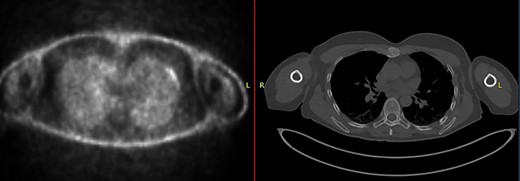

The second case at our institution was a 52-year-old woman with a history of left breast carcinoma treated for which she had undergone left wide local excision and sentinel node biopsy. Due to uncertainty regarding margins, she required a re-resection of her left breast tissue. She completed adjuvant radiotherapy and received maintenance hormonal therapy. She presented 8 months following her radiotherapy with sternal pain and positron emission tomography–computed tomography (PET–CT) imaging demonstrated localized uptake within the sternum (Fig. 3). Biopsy demonstrated proven recurrence of metastatic breast cancer. She was seen in clinic and counselled for partial sternectomy and reconstruction. She underwent partial sternectomy and underwent reconstruction with Synthes® plates. Her post-operative recovery was unremarkable. Post-operative histology was consistent with metastatic breast carcinoma, which was completely excised. The patient made an uncomplicated recovery and was seen in the outpatient clinic with a satisfactory post-operative chest radiograph (Fig. 4).

CT–PET demonstrating increased metabolic activity within the sternal lesion.